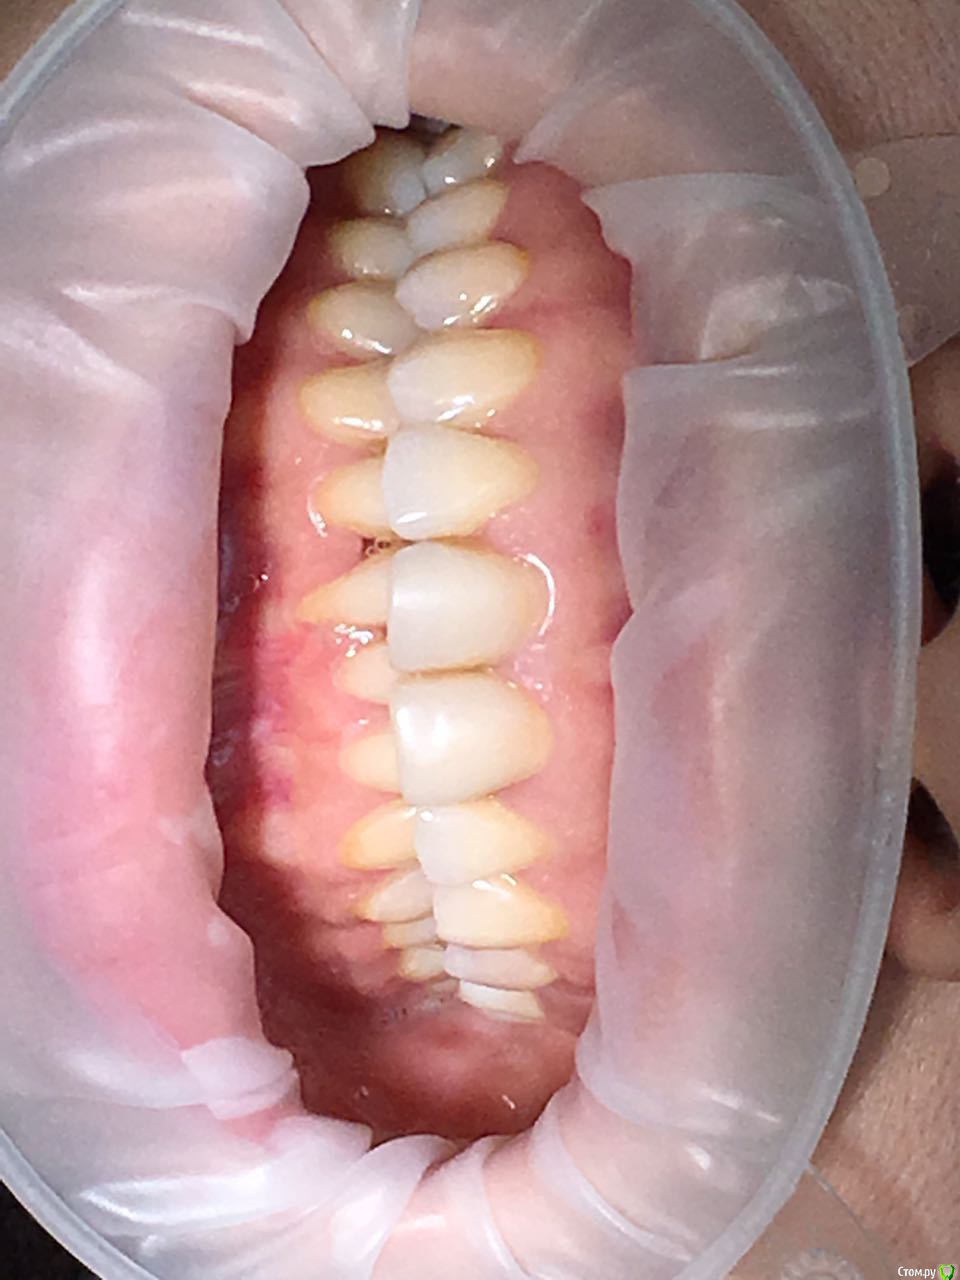

Kema Опубликовано 24 сентября, 2018 Поделиться Опубликовано 24 сентября, 2018 Здравствуйте, уважаемые профессионалы. Подскажите пожалуйста, нужна ли мне ортогнатическая операция? Ссылка на комментарий

Kema Опубликовано 25 сентября, 2018 Автор Поделиться Опубликовано 25 сентября, 2018 У меня нет нижней правой шестёрки. Правая восьмёрка подвинула семёрку, семёрка наклонилась. Левая ретинированная восьмёрка удалена. На правой стороне жевать неудобно. Ещё верхние зубы наклонились вперёд. Начитавшись про ортогнатические операции хотела узнать показана ли мне она. Ссылка на комментарий